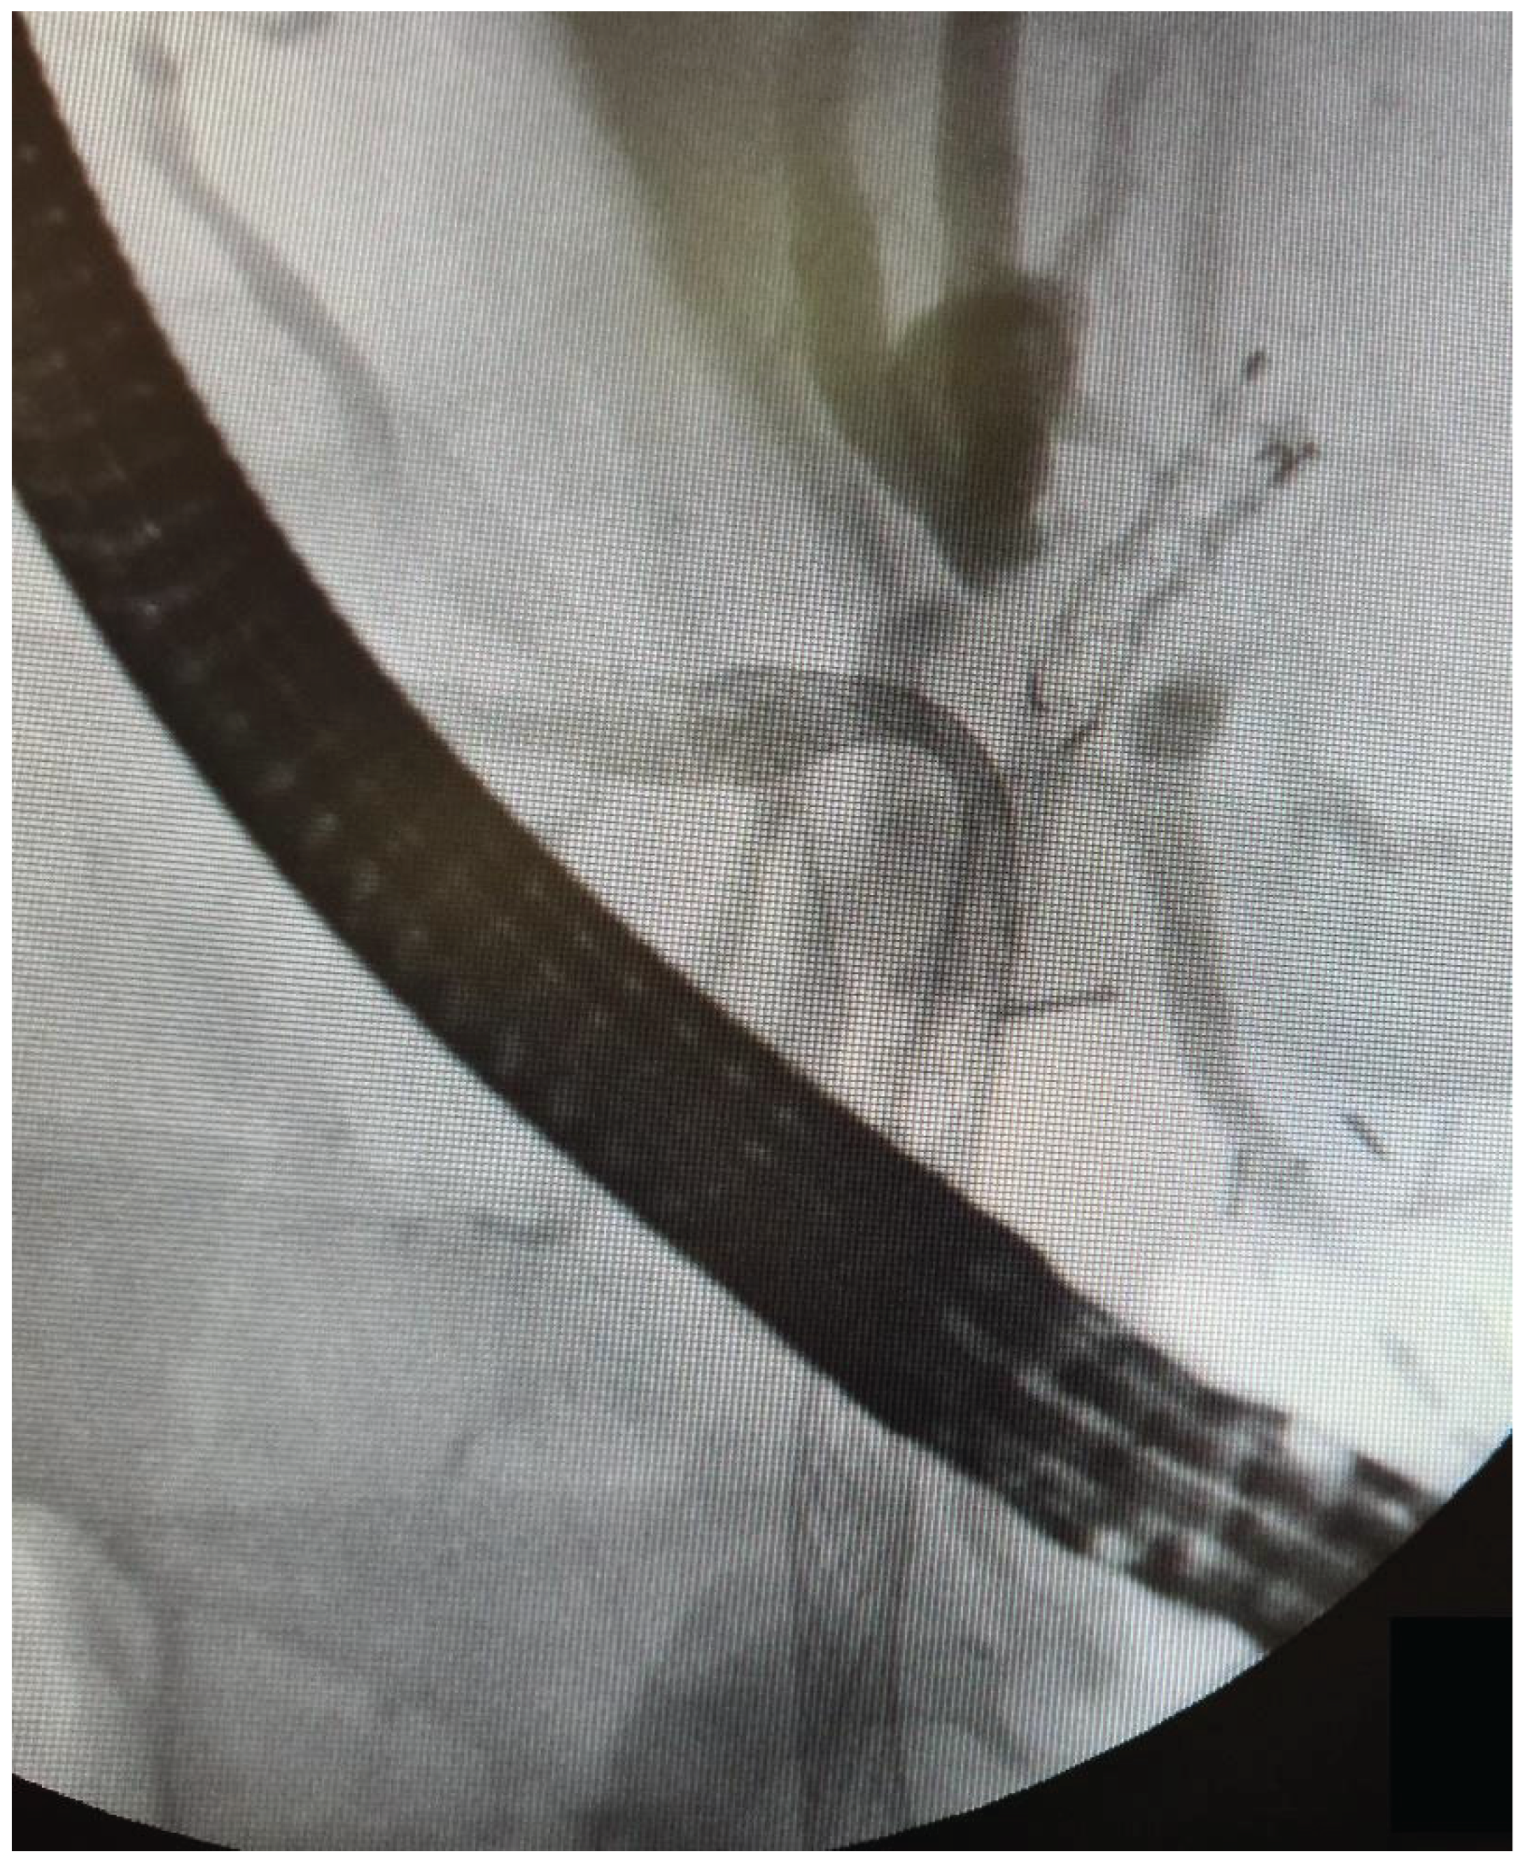

The data from 24 consecutive patients with bile duct stenosis due to non-resectable HC who underwent RFA with bile duct stenting in our department between 05.2020–05.2024 were collected retrospectively from electronic medical records and analyzed. Patients with malignant biliary stenosis had diagnoses of unresectable HC, PDAC in the head of the pancreas, and adenocarcinoma of the gallbladder. Inclusion criteria for RFA treatment included patients with recurrent mechanical jaundice due to cancer progression despite a previous biliary prosthesis. High-power radiofrequency ablation of the narrowed biliary segments, followed by reimplantation of SEMS, Amsterdam stents, or double pigtail (DPT) into their lumen, was performed in 24 patients (19 women and 5 men). The procedure was performed under intravenous sedation using a PENTAX-ED-34 and 10t2 duodenoscope. RFA was carried out with a power setting of 7–14 watts and a temperature of 75–80°C. The following stents were used for the procedure: uncovered SEMS (10x80 mm, 10x60 mm, 10x100 mm), Large Cell D-type stents (LCD) (10x60 mm), fully-covered SEMS (8x80 mm), Amsterdam-type plastic stents (12cm 10 Fr, 9cm 10 Fr, 12 cm 8.5 Fr, 12 cm 7 Fr), and self-expandable BIL-0-10-60-RP stents. Figures 2, 3, and 4 present the RFA catheter and stents’ configurations (Figure 2, Figure 3, Figure 4).

Figure 4. Stent-in-stent double SEMS configuration.